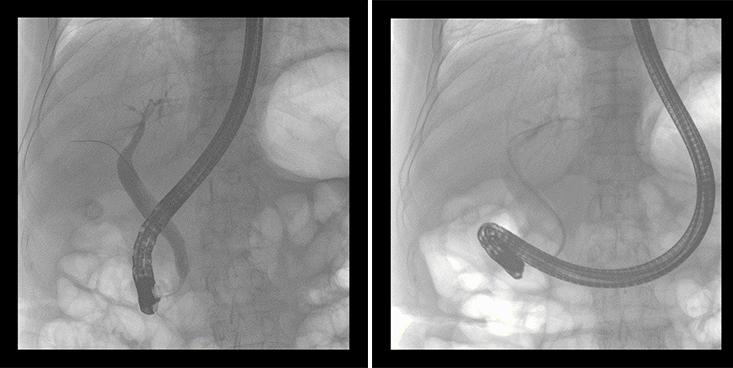

一位86歲的女性患者近來出現(xiàn)腹痛,入院后CT檢查并結(jié)合臨床表現(xiàn)被診斷為急性膽囊炎伴膽囊結(jié)石。經(jīng)專家團(tuán)隊(duì)協(xié)商并與患者家屬溝通,決定對(duì)患者實(shí)施經(jīng)內(nèi)窺鏡逆行胰膽管造影(ERCP)。

ERCP(經(jīng)十二指腸鏡下逆行胰膽管造影)現(xiàn)已成為比較成熟的微創(chuàng)介入技術(shù),被廣泛的應(yīng)用于臨床,ERCP也是消化內(nèi)鏡領(lǐng)域難度大、風(fēng)險(xiǎn)大、技術(shù)復(fù)雜的微創(chuàng)手術(shù),其并發(fā)癥多為致命性,ERCP手術(shù)對(duì)醫(yī)生的要求很高,因此,ERCP醫(yī)生又被稱為“刀尖上的舞者”。因?yàn)槭中g(shù)難度較大,過程復(fù)雜,需要C形臂精準(zhǔn)的配合,對(duì)影像清晰度的要求也非常高。

普愛醫(yī)療移動(dòng)式平板中C為本次ERCP手術(shù)提供實(shí)時(shí)無損高清影像,幫助醫(yī)生精準(zhǔn)定位?!俺上裥Ч浅0?!完全不輸國(guó)際大牌的醫(yī)學(xué)影像設(shè)備……”鼓樓醫(yī)院江北國(guó)際醫(yī)院內(nèi)鏡中心手術(shù)團(tuán)隊(duì)對(duì)普愛醫(yī)療移動(dòng)式平板中C的成像效果給與了高度的評(píng)價(jià)。

在消化內(nèi)科主任的領(lǐng)導(dǎo)和多科室全力配合下,南京鼓樓醫(yī)院江北國(guó)際醫(yī)院成功完成了首例ERCP手術(shù)。